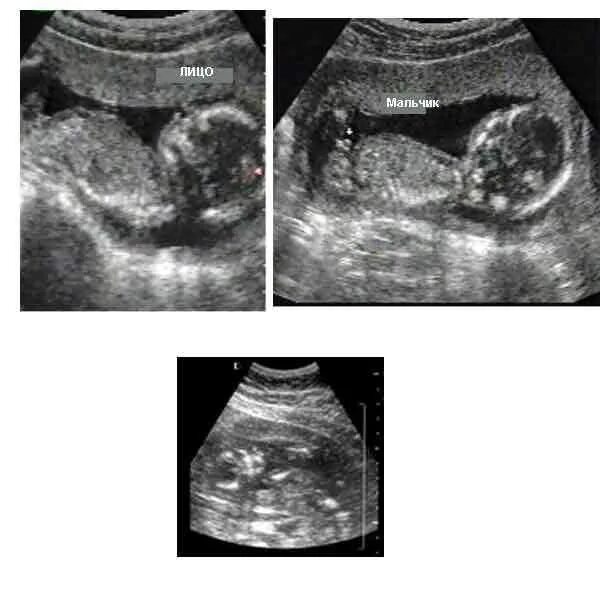

10 неделя пол ребенка